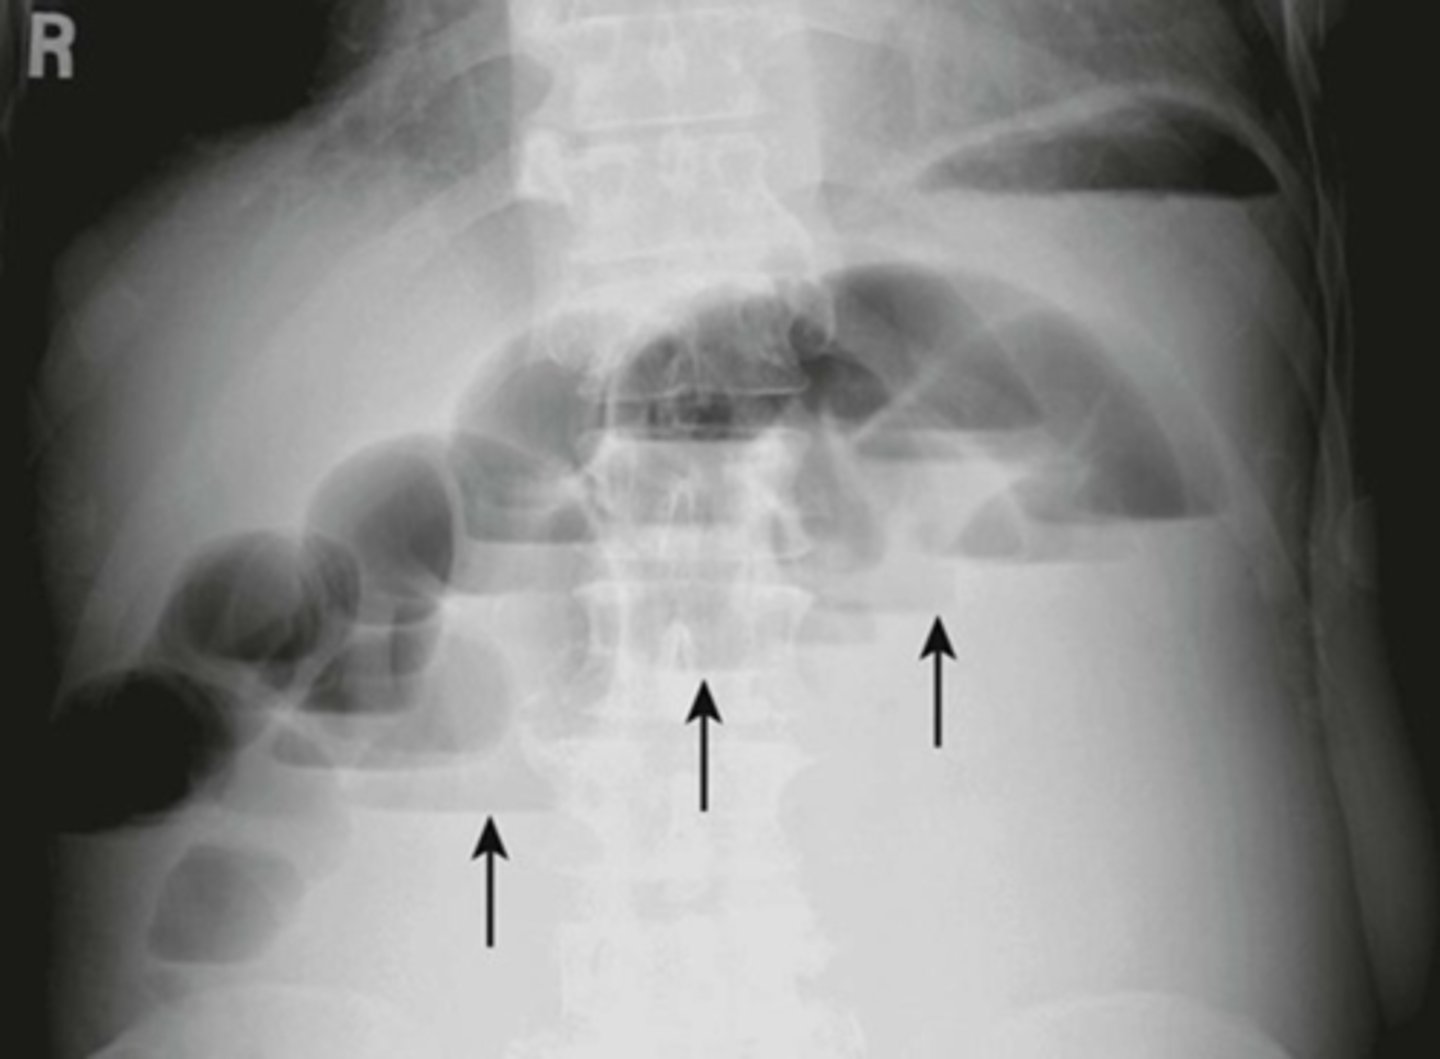

Pneumatosis - air in the abdominal wall.

WHITE ARROWS - RLQ demonstrating thin curvilinear lucency that parallels with the lumen of the adjacent bowel.

Appearance characteristic of gas in the bowel wall.

In infants the MC cause for this finding is necrotizing enterocolitis - a disease found mostly in premature infants in which the terminal ileum is most affected.

Pneumatosis intestinalis is pathognomonic for necrotizing enterocolitis in infants.